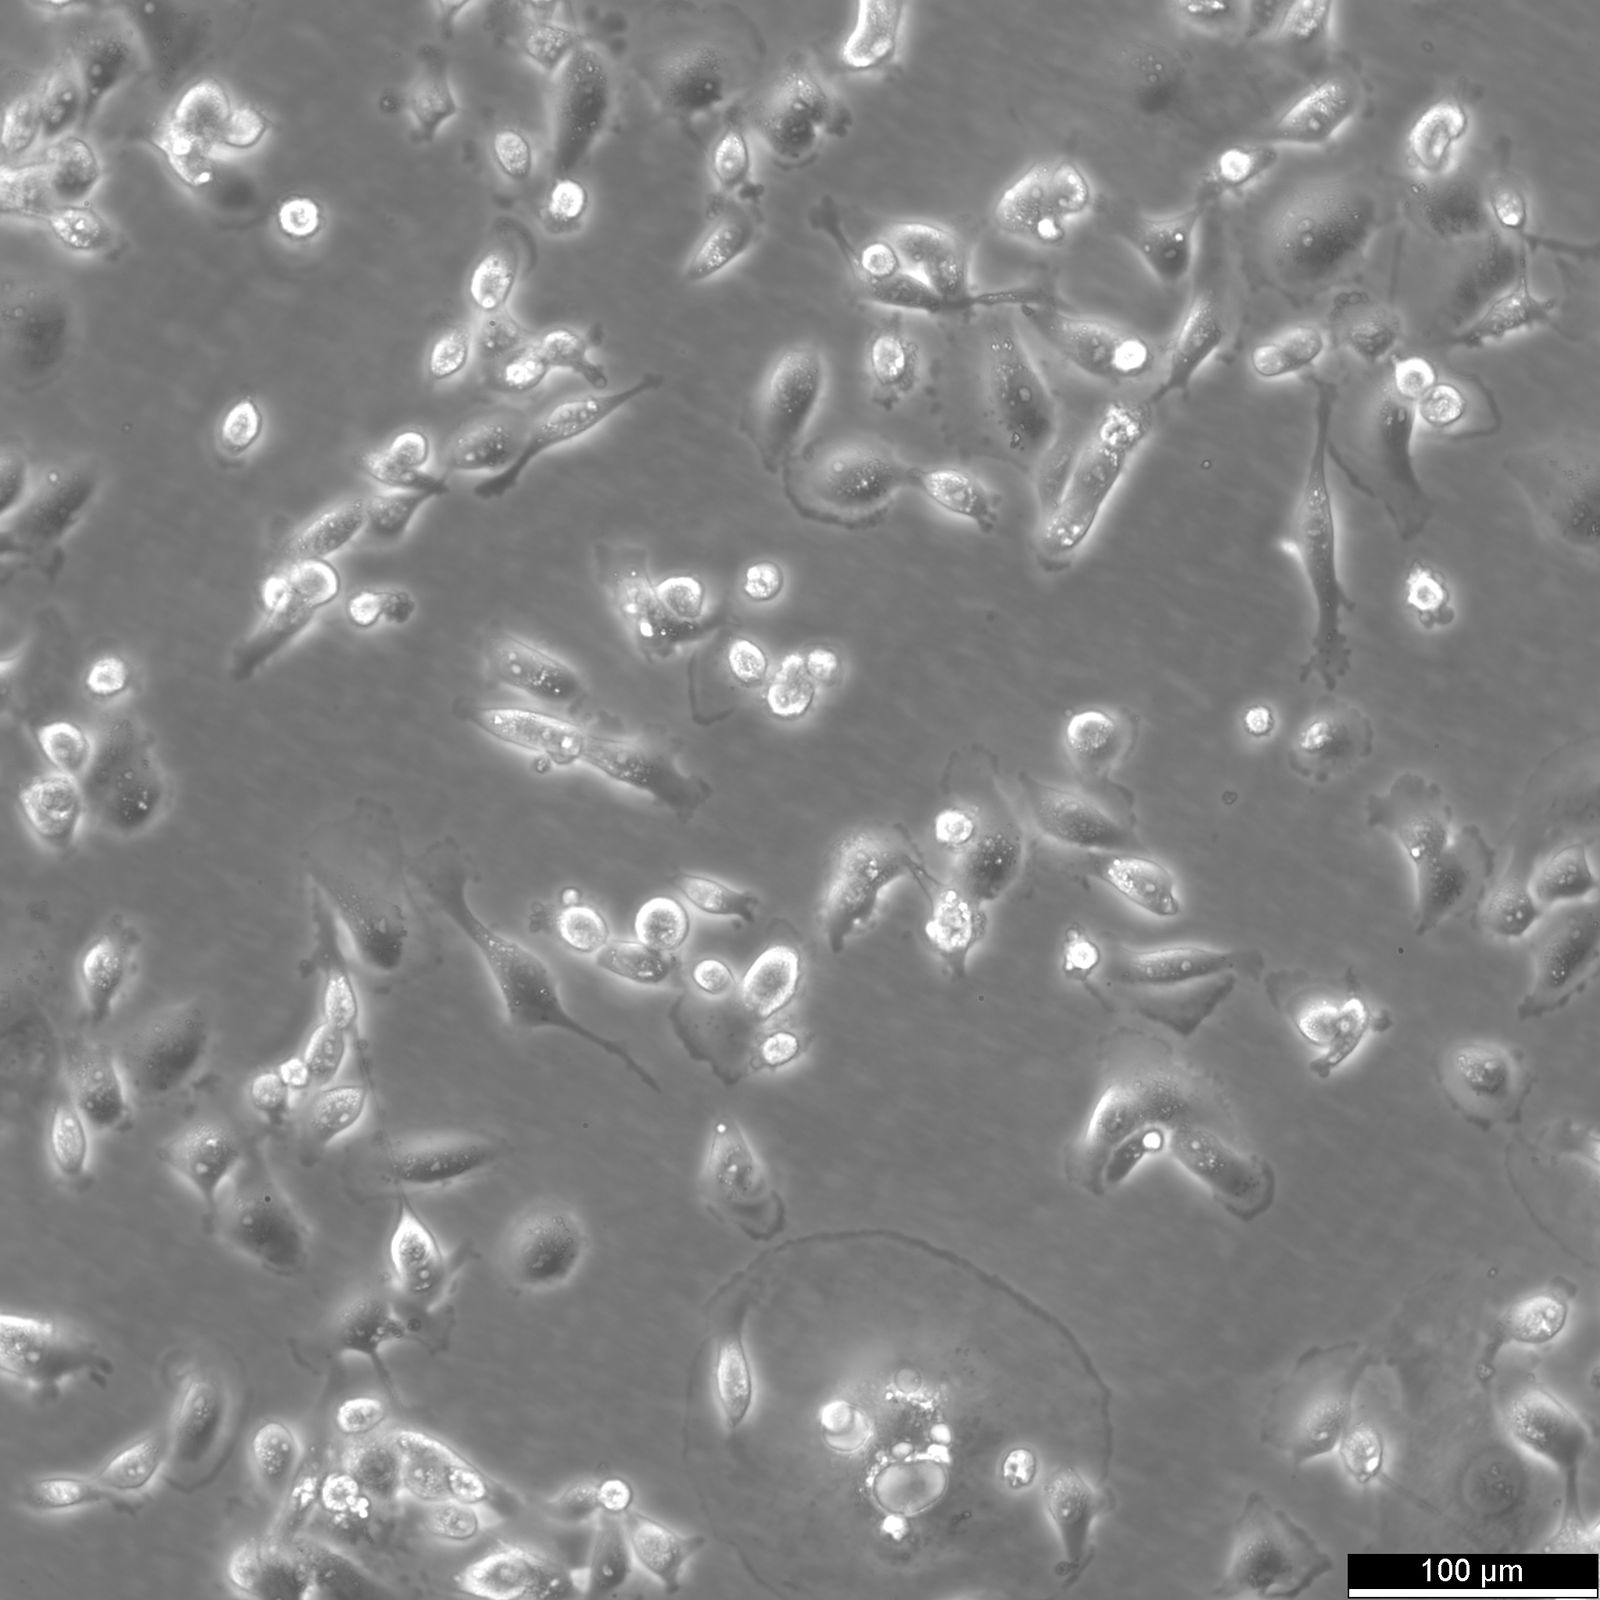

Categories: Breast cancer cell lines Description: The MDA-MB-231 cell line is a widely used model in breast cancer research. Derived from a human breast adenocarcinoma, these cells are characterized by their aggressive and invasive nature, making them an ideal model for studying triple-negative breast cancer (TNBC). MDA-MB-231 cells lack estrogen receptors (ER), progesterone receptors (PR), and HER2 amplification, which are typical markers used to classify and treat breast cancers. Consequently, these cells are resistant to hormonal therapies, reflecting the clinical challenges faced in managing TNBC. Their mesenchymal-like phenotype and ability to form tumors in immunocompromised mice further contribute to their utility in cancer research. Genetically, MDA-MB-231 cells harbor mutations in key oncogenes and tumor suppressor genes such as TP53, KRAS, and BRAF. These genetic alterations play a crucial role in driving their malignancy and metastatic potential. Researchers use this cell line to investigate the molecular mechanisms underlying cancer progression, metastasis, and drug resistance. MDA-MB-231 cells are also employed in high-throughput screening for potential therapeutic agents, as their aggressive behavior provides a stringent test for new anti-cancer drugs. The cell line's robust response to various stimuli makes it an invaluable tool for deciphering the complex biology of triple-negative breast cancer. Organism: Human Tissue: Breast Disease: Adenocarcinoma Metastatic Site: Pleural effusion Synonyms: MDA_MB_231, MDA-MB 231, MDA.MB.231, MDA MB 231, MDA MB231, MDA Mb231, MDA-MB231, MDAMB-231, MDAMB231, MDA-231, MDA-231P, MDA231, MDA231-BRE, MB231, MD Anderson-Metastatic Breast-231 Age: 51 years Gender: Female Ethnicity: European Morphology: Epithelial Growth Properties: Adherent Citation: MDA-MB-231 (Cytion catalog number 300275) Biosafety Level: 1 Ncbi_ Taxid: 9606.0 Cellosaurus Accession: CVCL_0062 Culture Medium: DMEM:Ham's F12 (1:1), w: 3.1 g/L Glucose, w: 2.5 mM L-Glutamine, w: 15 mM HEPES, w: 0.5 mM Sodium pyruvate, w: 1.2 g/L NaHCO3 (Cytion article number 820400a) Supplements: Supplement the medium with 5% FBS Dissociation Reagent: Accutase Subculturing: Remove the old medium from the adherent cells and wash them with PBS that lacks calcium and magnesium. For T25 flasks, use 3-5 ml of PBS, and for T75 flasks, use 5-10 ml. Then, cover the cells completely with Accutase, using 1-2 ml for T25 flasks and 2.5 ml for T75 flasks. Let the cells incubate at room temperature for 8-10 minutes to detach them. After incubation, gently mix the cells with 10 ml of medium to resuspend them, then centrifuge at 300xg for 3 minutes. Discard the supernatant, resuspend the cells in fresh medium, and transfer them into new flasks that already contain fresh medium. Fluid Renewal: 2 to 3 times per week Freeze Medium: As a cryopreservation medium, use complete growth medium (including FBS) + 10% DMSO for adequate post-thaw viability, or CM-1 (Cytion catalog number 800100), which includes optimized osmoprotectants and metabolic stabilizers to enhance recovery and reduce cryo-induced stress. Thawing And Culturing Cells: Confirm that the vial remains deeply frozen upon delivery, as cells are shipped on dry ice to maintain optimal temperatures during transit. Upon receipt, either store the cryovial immediately at temperatures below -150°C to ensure the preservation of cellular integrity, or proceed to step 3 if immediate culturing is required. For immediate culturing, swiftly thaw the vial by immersing it in a 37°C water bath with clean water and an antimicrobial agent, agitating gently for 40-60 seconds until a small ice clump remains. Perform all subsequent steps under sterile conditions in a flow hood, disinfecting the cryovial with 70% ethanol before opening. Carefully open the disinfected vial and transfer the cell suspension into a 15 ml centrifuge tube containing 8 ml of room-temperature culture medium, mixing gently. Centrifuge the mixture at 300 x g for 3 minutes to separate the cells and carefully discard the supernatant containing residual freezing medium. Gently resuspend the cell pellet in 10 ml of fresh culture medium. For adherent cells, divide the suspension between two T25 culture flasks, for suspension cultures, transfer all the medium into one T25 flask to promote effective cell interaction and growth. Adhere to established subculture protocols for continued growth and maintenance of the cell line, ensuring reliable experimental outcomes. Sterility: Mycoplasma contamination is excluded using both PCR-based assays and luminescence-based mycoplasma detection methods. To ensure there is no bacterial, fungal, or yeast contamination, cell cultures are subjected to daily visual inspections. Safety Precautions: When planning to store a cryovial in liquid nitrogen for future thawing, it is mandatory to adhere to stringent safety measures. Appropriate protective gloves and clothing are essential, and the use of a face mask or safety goggles is required during the transfer of frozen samples to or from the liquid nitrogen tank. This is to mitigate the risk of injury from potential cryovial explosions upon removal, which can result in the projection of sharp fragments. Warranty: We stand by the promise of delivering products with high cell viability and robust culture performance. To achieve the best results, please make sure you follow the storage and culture instructions detailed in the product information sheet closely. Your adherence to these guidelines is key to success. Subject To Material Transfer Agreements: If you intend to use Cytion cell lines solely for internal research at a single research site, please complete and sign our Material Transfer Agreement (MTA) and submit it along with your order.For any commercial applications - including but not limited to fee-for-service work, quality control testing, product release, diagnostic use, or regulatory studies - please complete the Intended Use Form so we can prepare a suitable agreement tailored to your project.Please note: The MTA applies only to certain cell lines. If this notice and the MTA document appear on a product page, the agreement is applicable. For cell lines not covered by the MTA, no reference to the agreement will be shown. The MTA is not valid for customers in the Americas, China, or Taiwan. Please contact our U.S. entity to receive the appropriate agreement. Required Product 1: 820400a Required Product 3: 860015.0 Required Product 4: 830100.0